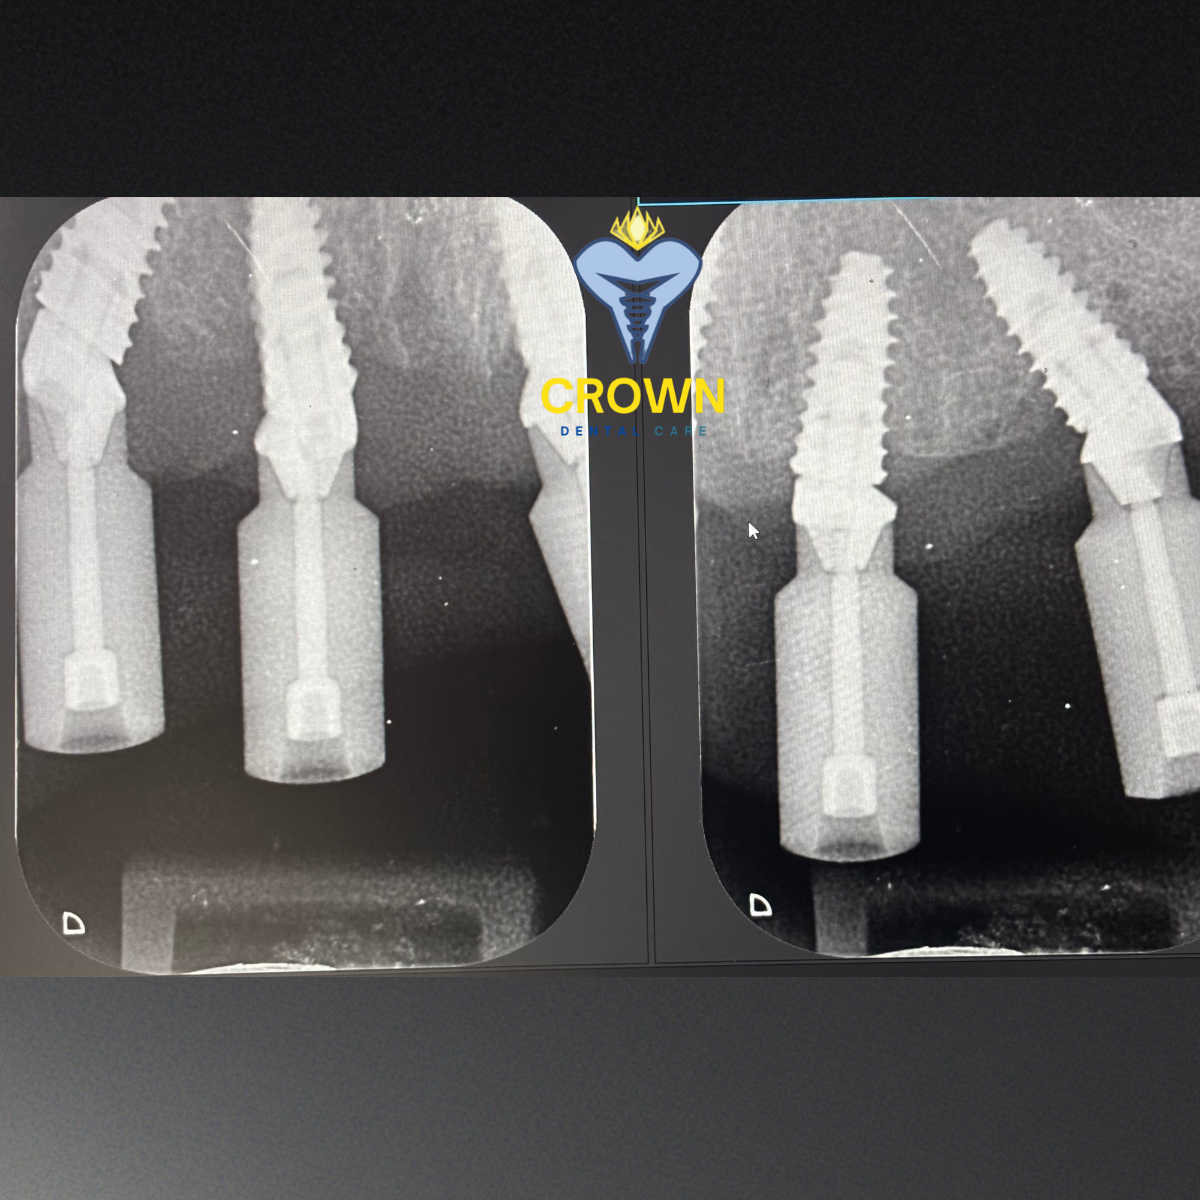

Implant Precision X-Ray

Full-arch implant restorations demand absolute precision. Now, Crown Dental Care delivers exactly that for both flagship procedures.

All-on-4™

Captures all 4 implant positions simultaneously—no sequential stitching errors. Tilt angles are reproduced to within fractions of a degree in the digital model, ensuring the prosthesis fits passively on first placement with no chairside adjustments.

All-on-6™

Six-point spatial mapping eliminates arch distortion in wider jaws. Greater distribution of masticatory load is backed by precision-fit prosthetics, providing exceptional long-term stability for patients with heavy occlusal demands.